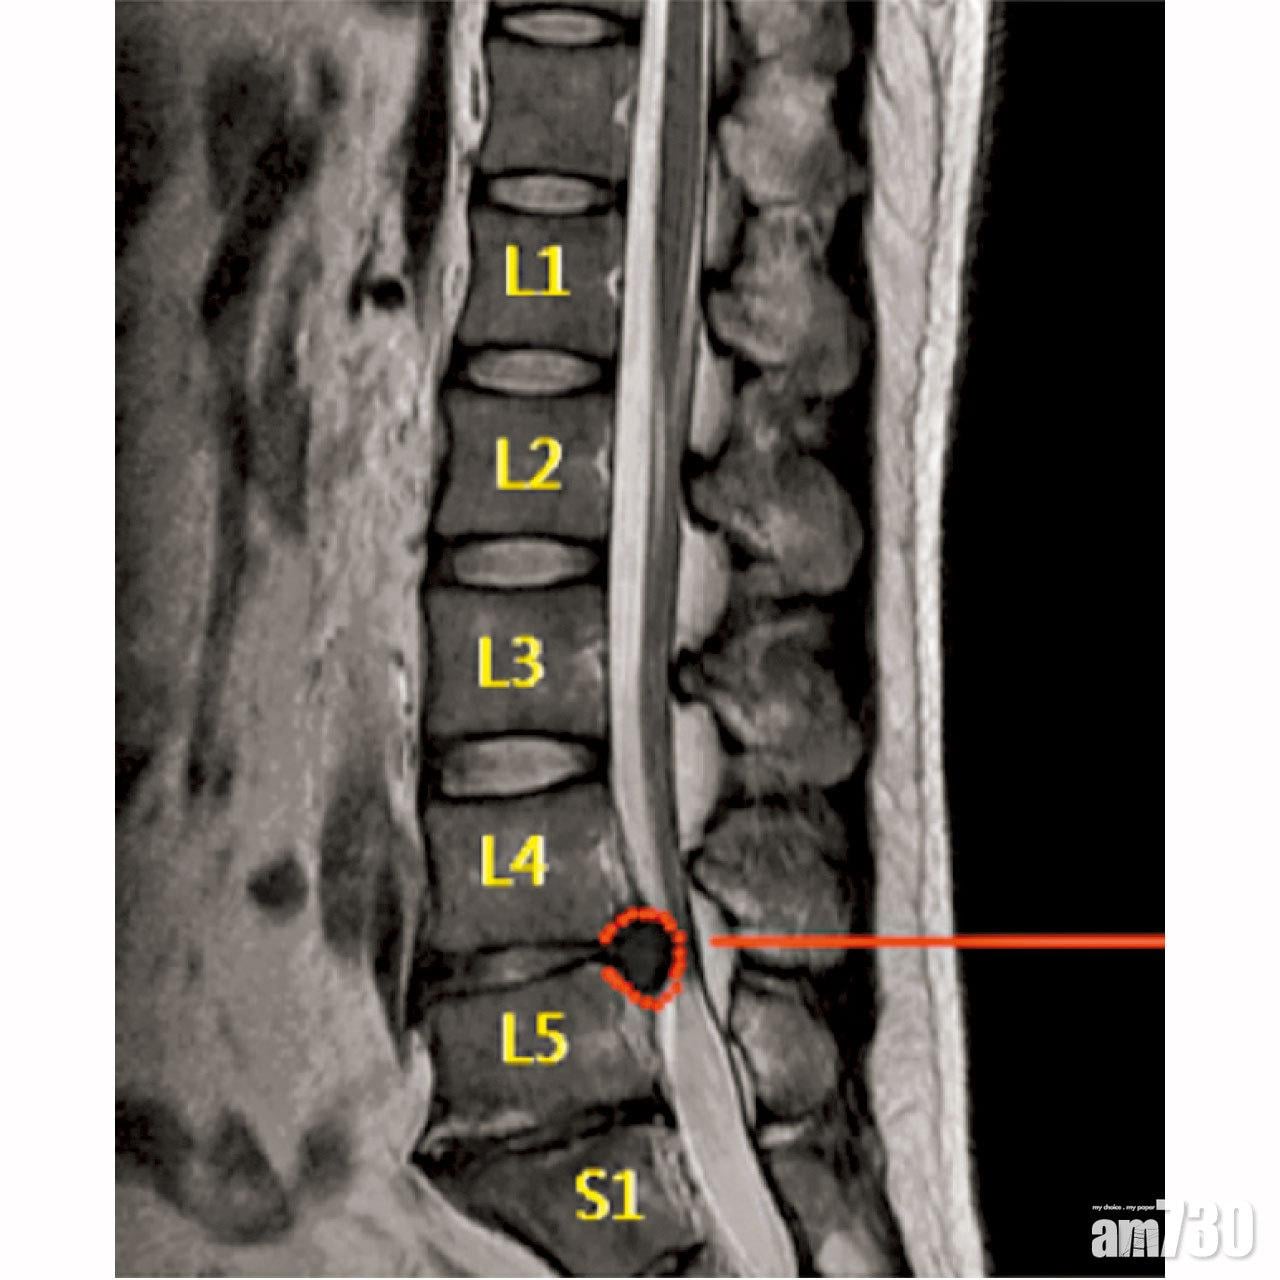

對於此症因何會嚴重至要做手術,嚴永藝解釋,那是基於受影響腰椎位置及突出範圍,如發生在L4-5或L5S1腰椎,會引致腳掌或腳趾無力,甚至無法抬起腳;若壓著神經末端的馬尾神經,便影響大小便功能和令肛門口麻痺,此時便急需做手術切除突出的椎間盤,一旦延遲,大小便功能或無法恢復。

他便曾有個案是健身教練,患者一直有腰痛,一次在家不小心扭到腰骨後便腳痛,看醫生食藥都無改善,更痛到無法走路,經磁力共振檢查後,確診L5S1節有嚴重椎間盤突出。患者接受新式手術治療後,腳痛隨即紓減,翌日出院,一星期後已可去旅行。

椎間盤突出壓著神經線,嚴重可致影響活動,要動手術治療。